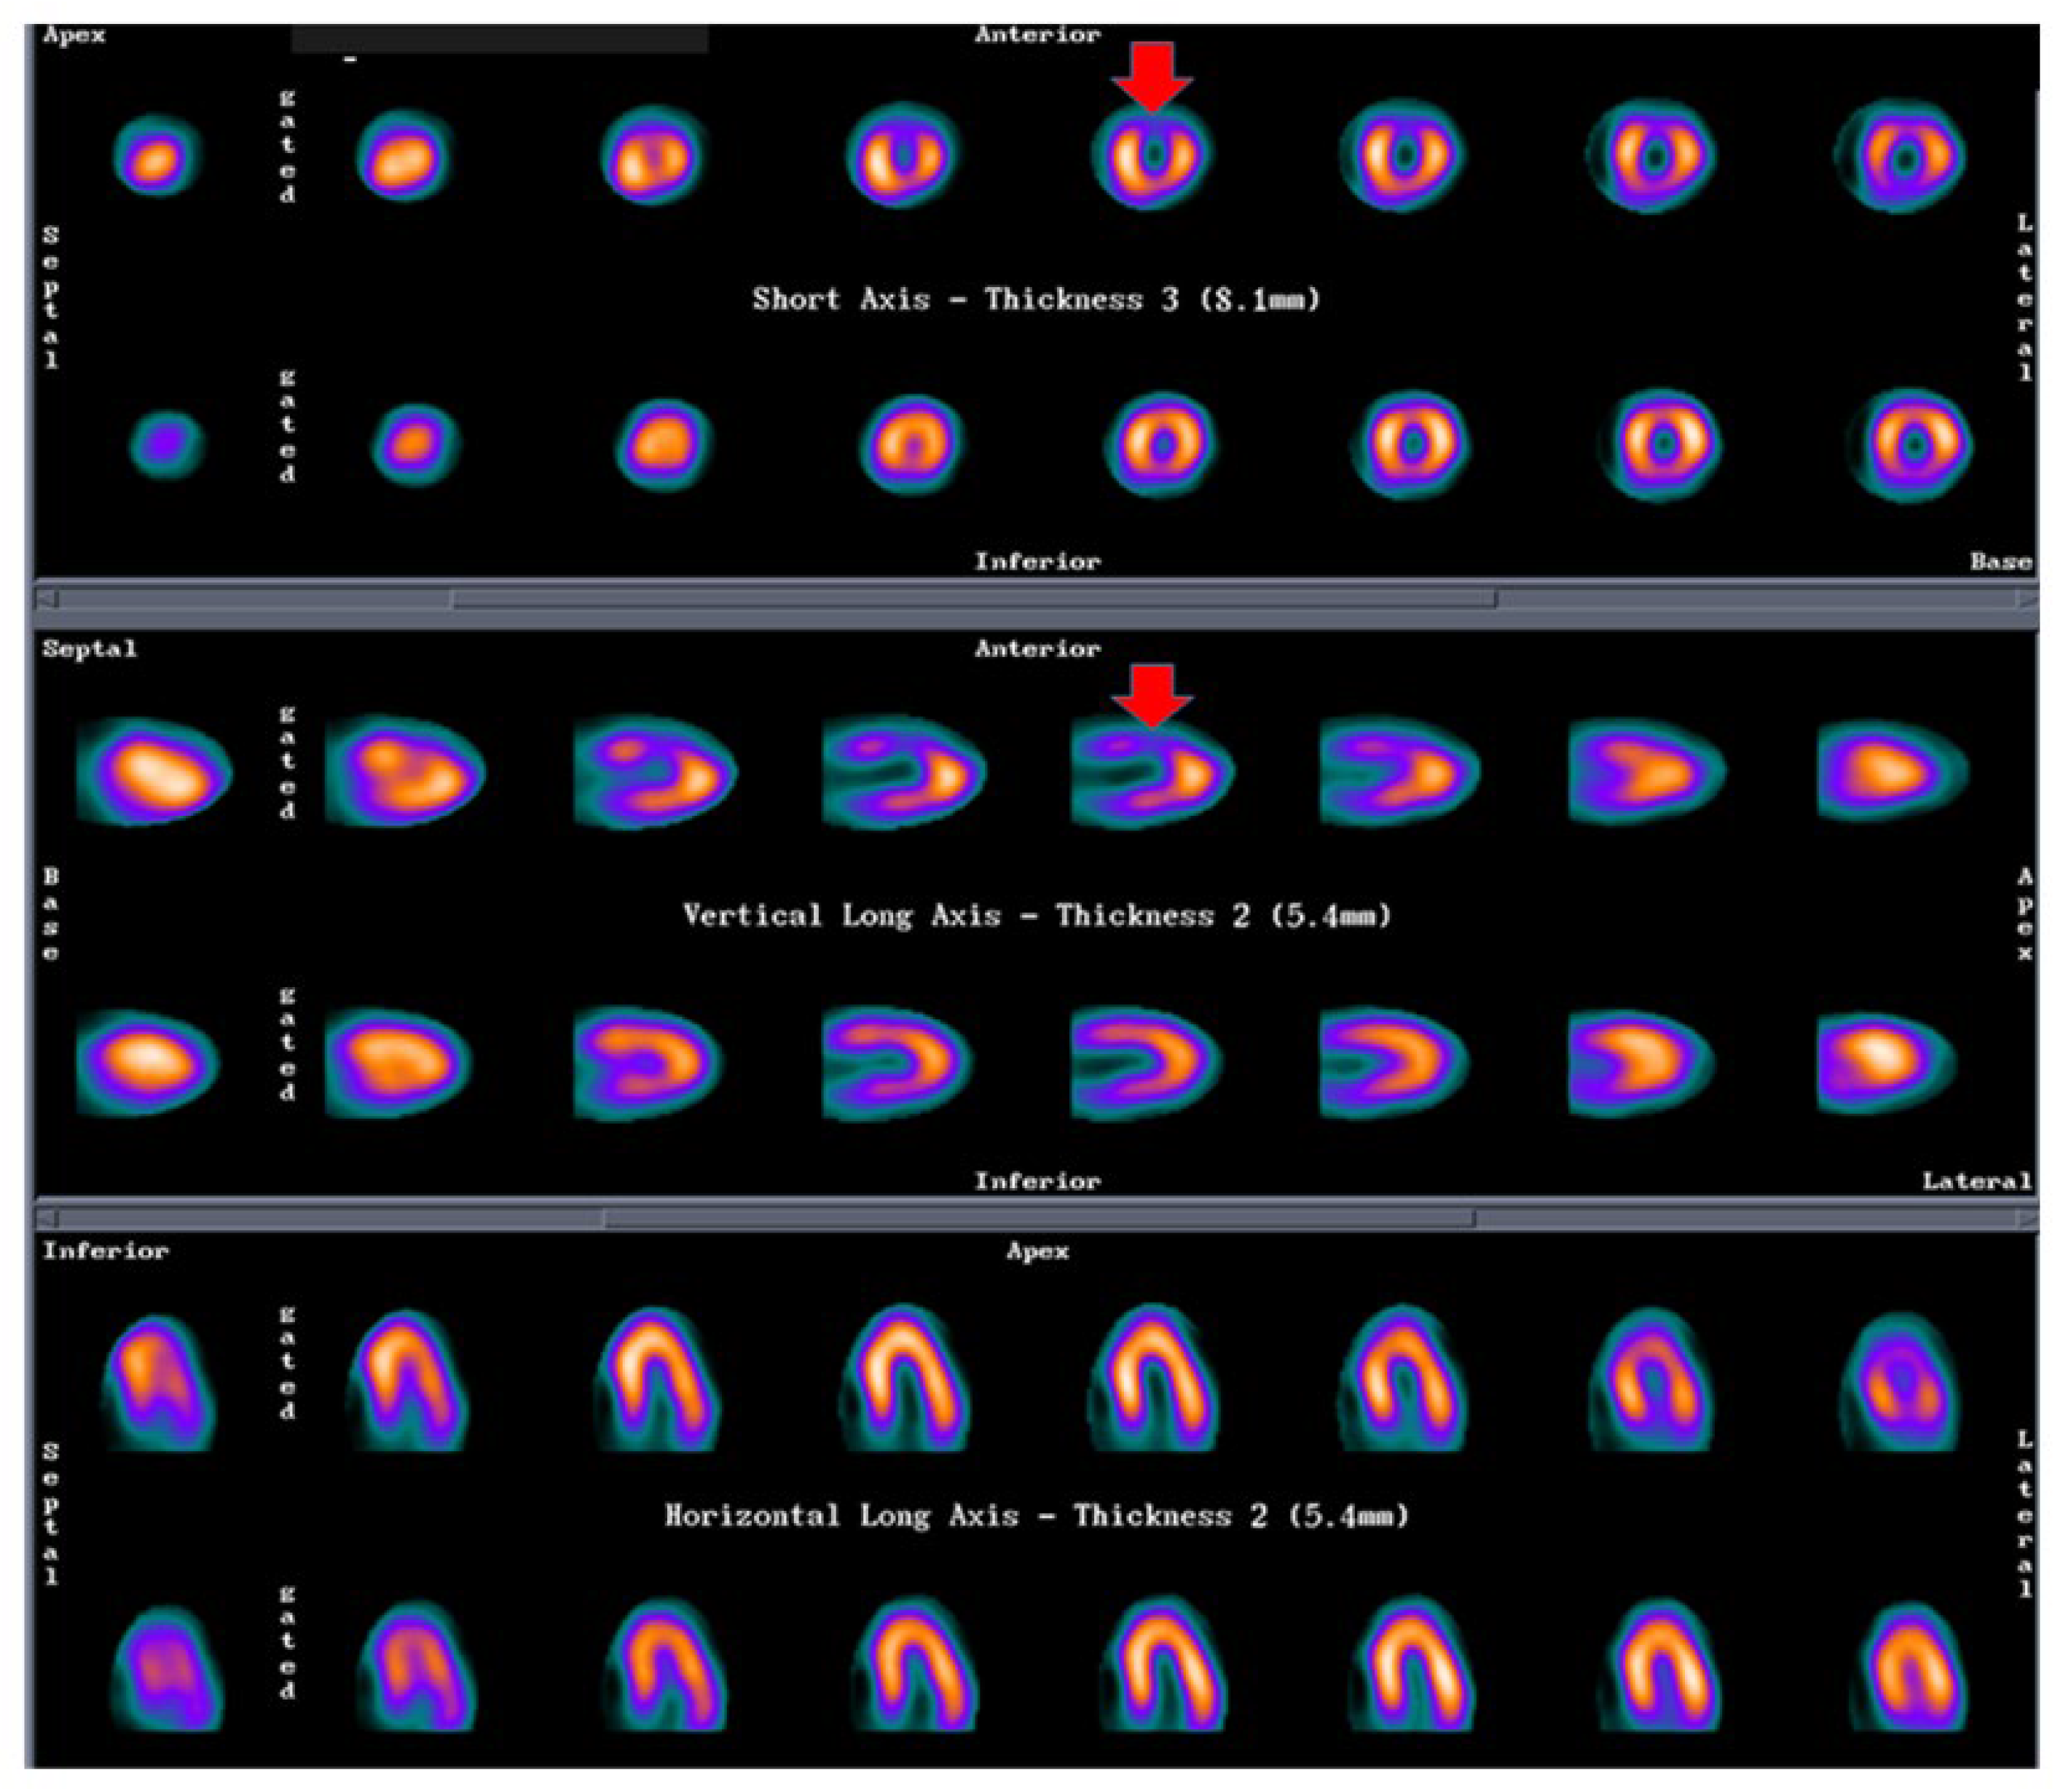

Figure 2 shows a case of a female patient with multiple RFs and history of chest pain with several hospital admissions. The invasive angiography did not show lesions on epicardial coronary arteries. A PET study rest/stress test with dipyridamole was performed and the CFR was reduced in all the territories, compatible with a microvascular dysfunction.

Figure 2.

PET MPI in a patient with microvascular dysfunction. Legend: Female, 66 y.o., history of HBP, dyslipidemia, ex-smoker, early menopause. History of chest pain with several hospital admissions. Epicardial coronary arteries without lesions on invasive angiography. A PET study with stress/rest protocol with dipyridamole (0.56 mg/kg) was performed. Stress/rest images show a normal perfusion. Stress LVEF: 52%. Myocardial blood flow analysis shows a significant reduction of CFR, mainly in the LAD territory. Compatible with a microvascular dysfunction. HBP: high blood pressure; PET: positron emission tomography; LVEF: left ventricular ejection fraction; CFR: coronary flow reserve; LAD: left anterior descendent coronary artery; RCA: right coronary artery; Cx: left circumflex coronary artery. Image courtesy of Dr. Roberto Agüero, Fundación Centro Diagnóstico Nuclear, Buenos Aires, Argentina.

Mental stress-induced myocardial ischemia can be a common manifestation of INOCA in women [24,77], which can be diagnosed by a reduction of LVEF, new regional wall motion abnormalities or a perfusion defect in response to mental stress. In a small group of postmenopausal women with typical angina and normal coronary angiography studied via 99mTc methoxy-isobutyl-isonitrile SPECT MPI (exercise stress/rest/mental stress protocol) and brachial artery endothelial function measurement via ultrasonography, we found a physical stress-induced ischemia (concordant with mental stress-induced ischemia, see Figure 3) associated with post-stress LVEF reduction and endothelial dysfunction (abnormal flow-mediated vasodilation) in 37% of patients [78].

Figure 3.

SPECT MPI in a patient with mental stress induced ischemia. Legend: Female, 57 y.o., postmenopausal, HBP. Angina with epicardial coronary arteries without lesions. Stress ECG: 1.5 mm ST depression, V1–V4. SPECT-MPI: Physical stress-induced ischemia (concordant with mental stress-induced ischemia). First line of each projection shows mental stress images, second line shows rest images. Compatible with anterior ischemia. This patient also had endothelial dysfunction measured as abnormal flow-mediated vasodilation in brachial artery with ultrasound. HBP: high blood pressure; ECG: electrocardiogram; SPECT: single photon emission tomography; MPI: myocardial perfusion imaging.